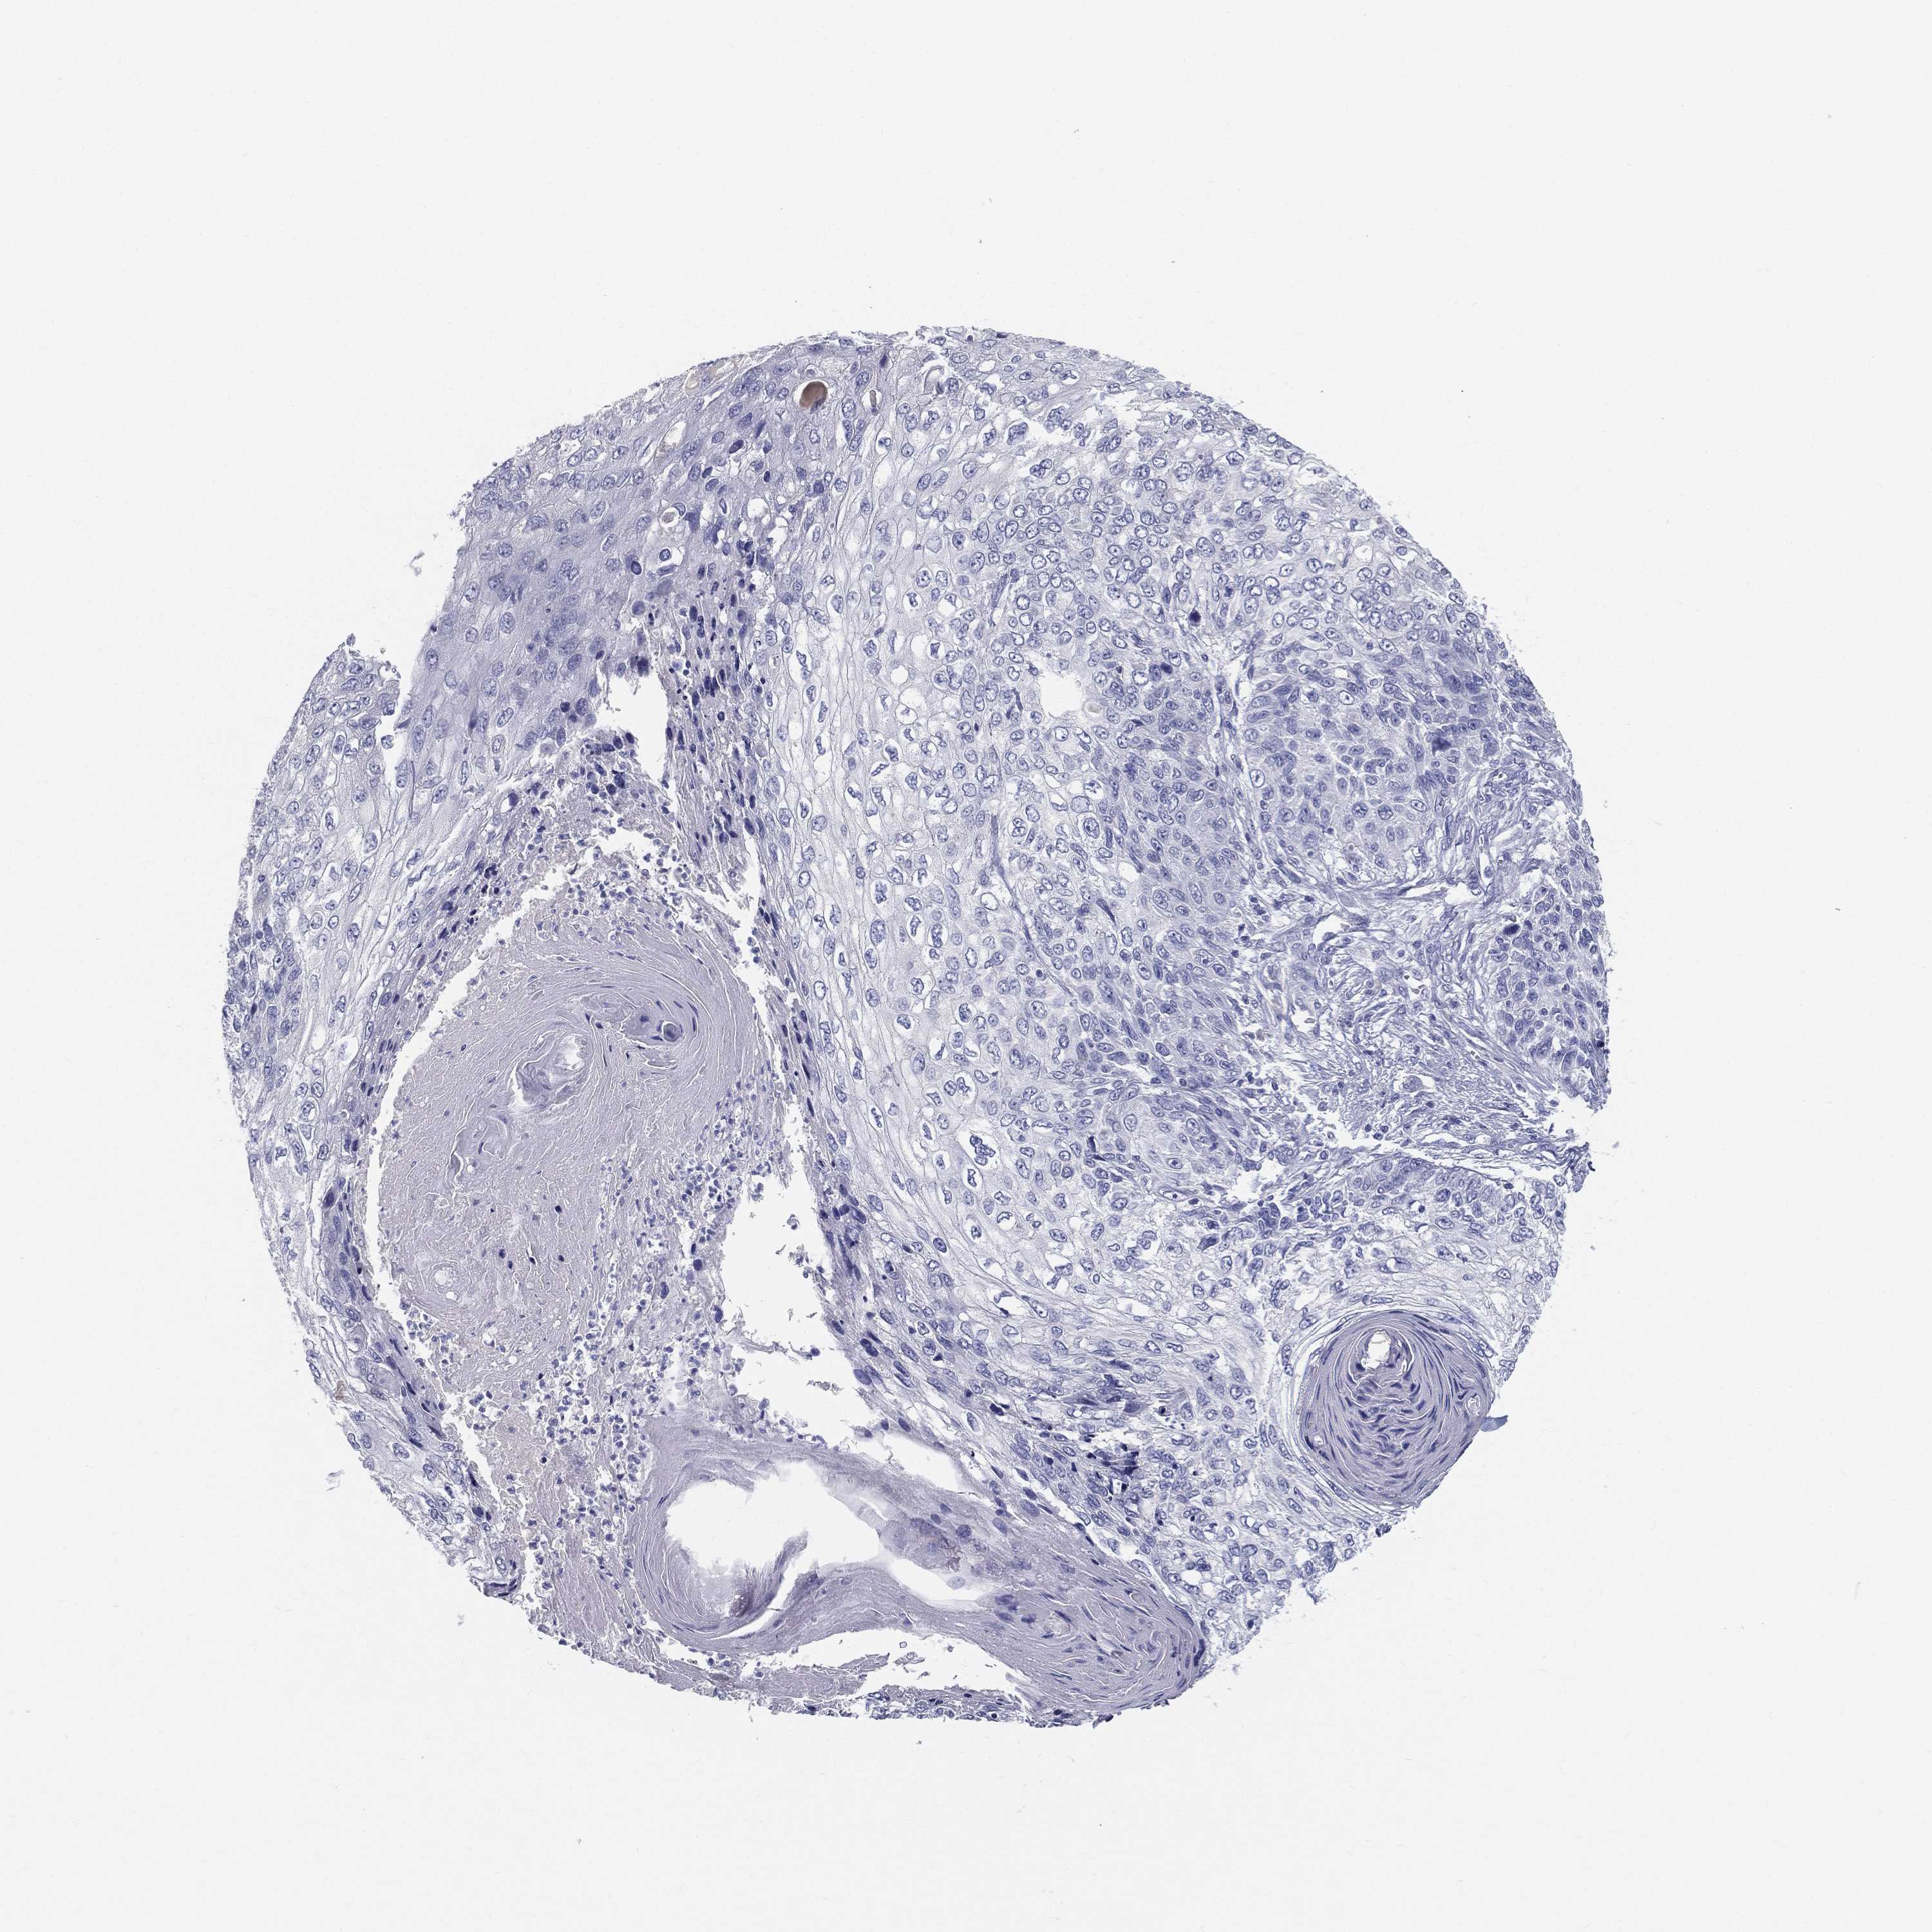

Basal cell and squamous cell cancer

SKIN CANCER - Protein expressioni

A mouse-over function shows sample information and annotation data. Click on an image to view it in a full screen mode. Samples can be filtered based on level of antibody staining by selecting one or several of the following categories: high, medium, low and not detected. The assay and annotation is described here.

Antibody stainingi

Antibody staining in the annotated cell types in the current human tissue is reported as not detected, low, medium, or high, based on conventional immunohistochemistry profiling in selected tissues. This score is based on the combination of the staining intensity and fraction of stained cells.

Each image is clickable and will lead to virtual microscopy that enables deeper exploration of all samples and also displays staining intensity scores, fraction scores and subcellular localization as well as patient and tissue information for each sample.

Antibody HPA002904

Staining

High

Medium

Low

Not detected

Intensity

Strong

Moderate

Weak

Negative

Quantity

>75%

75%-25%

<25%

None

Location

Nuclear

Cytoplasmic/membranous

Cytoplasmic/membranous,nuclear

Basal cell carcinoma

Squamous cell carcinoma, NOS